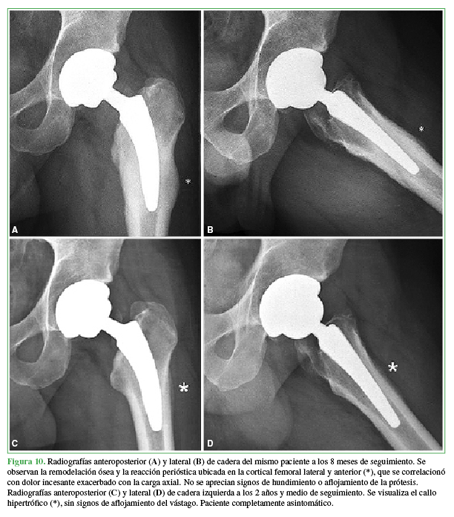

La ATC con una prótesis de vástago corto ya ha demostrado excelentes resultados clínicos y radiológicos a mediano y largo plazo61,62 resultados variables de supervivencia entre el 92,2% y el 100%.63,64,65,66 Sin embargo, no todos los diseños son similares en tamaño y forma;13 por lo tanto, distintas distribuciones de carga hacia el fémur proximal pueden desencadenar diferentes patrones de remodelación ósea, generando diferentes resultados clínicos y radiológicos.13,33Cuando se diagnostica dolor de muslo posoperatorio, entender sus etiologías potenciales es fundamental para seleccionar la modalidad de tratamiento adecuada. Originalmente, se intentó disminuir la rigidez estructural con diseños modernos de vástagos no cementados;67 sin embargo, la transferencia de tensión excesiva derivada de un desajuste en la rigidez a la flexión ha sido una preocupación en términos de alteraciones mecánicas en el módulo de elasticidad del fémur proximal, y la generación de dolor es una consecuencia potencial.67,68 Con el advenimiento de los vástagos cortos, muchas investigaciones han centrado su atención en el dolor de muslo y han aparecido muchas teorías más recientes para explicar su génesis.13,33 En algunas situaciones, las radiografías posoperatorias pueden mostrar hipertrofia cortical como consecuencia de la remodelación ósea que casi siempre es un evento asintomático. Maier y cols. han analizado los resultados clínicos y radiológicos de sus primeras 100 ATC consecutivas con el vástago Fitmore® (Zimmer, Warsaw, IN, EE.UU.).69 Tras un seguimiento medio de 3.3 años (rango 2-4.4), la supervivencia fue del 100% tomando la revisión por cualquier motivo como falla, sin reportar aflojamiento del componente femoral. Sin embargo, se observó una hipertrofia cortical en 50 caderas, predominantemente en las zonas 3 y 5 de Gruen.47,69De ellos, dos pacientes refirieron dolor moderado en el muslo que se agudizó durante el ejercicio físico. Dicho esto, en la Argentina, se ha reportado un caso de fractura por estrés inusual en un hombre de 43 años de edad, golfista profesional, en la punta distal lateral de un vástago corto no cementado con fijación metafisaria70 (Figura 10).